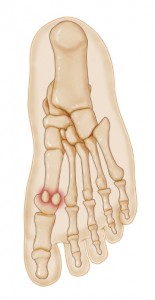

دنیای اطلاعات: استخوانهای سزموئید (sesamoid bones) استخوانهای کوچکی هستند که در لابه لای وتر اتصال عضلانی وتری قرار دارند. استخوانهای سزموئید باعث افزایش مزیت مکانیکی و محافظت از اتصالات عضلانی وتری میشوند. البته جزءدستهبندی اصلی استخوانها قرار ندارند.

استخوان سزموئید استخوانی تعبیه شده در یک تاندون یا یک عضله است. با توجه به اندازه کوچک اغلب سزموئیدها نام (دانه کنجدی) از کلمه لاتین “sesamum” (sesame seed) مشتق شده است، در بعضی اوقات این استخوان به فشارهای وارده واکنش نشان می دهد.

استخوان سزموئید